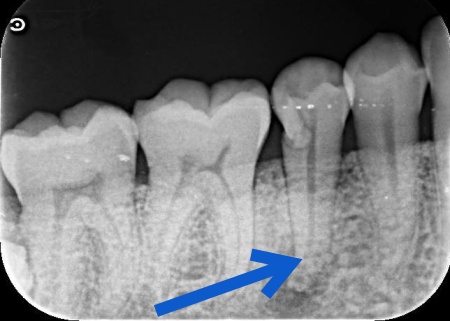

| 主訴 | 「右下の歯ぐきが腫れているのが気になる」とご相談いただきました。 |

| 診断 | 拝見したところ、右下奥歯の根元の歯ぐきに腫れが見られました。 原因を調べるためにレントゲン検査を行ったところ、歯の根の先に炎症が起きている様子が確認できました。 さらに詳しく調べた結果、歯根の壁に穴があくパーフォレーションが起きており、その穴から細菌が入り込んで歯根の周囲に感染と炎症が広がっていると考えられます。 パーフォレーションとは、歯の内部にある神経の通り道と歯の外側を隔てている壁に穴があいてしまう状態のことです。 このまま放置すると、炎症がさらに広がり歯を残すことが難しくなる可能性があることから、できるだけ早めに処置を行う必要があると診断しました。 |

治療前